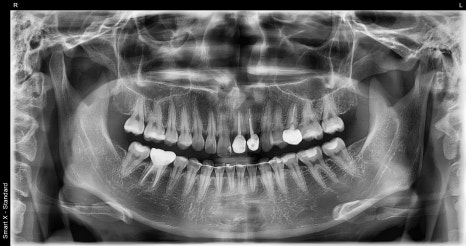

초진 시 파노라마와 구강 사진을 촬영해

전체 치아 상태를 확인했고,

특히 앞니 라인의 색·투명도·대칭이

전체적인 인상을 좌우하고 있어

라미네이트와 전치부 크라운을 조합한

설계가 가장 적합하다고 판단했습니다.